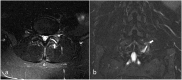

Low back pain (LBP) is the most common pain syndrome, and is an enormous burden and cost generator for society. Lumbar facet joints (FJ) constitute a common source of pain, accounting for 15-45% of LBP. Facet joint degenerative osteoarthritis is the most frequent form of facet joint pain. History and physical examination may suggest but not confirm facet joint syndrome. Although imaging (radiographs, MRI, CT, SPECT) for back pain syndrome is very commonly performed, there are no effective correlations between clinical symptoms and degenerative spinal changes. Diagnostic positive facet joint block can indicate facet joints as the source of chronic spinal pain. These patients may benefit from specific interventions to eliminate facet joint pain such as neurolysis, by radiofrequency or cryoablation. The purpose of this review is to describe the anatomy, epidemiology, clinical presentation, and radiologic findings of facet joint syndrome. Specific interventional facet joint management will also be described in detail. TEACHING POINTS: • Lumbar facet joints constitute a common source of pain accounting of 15-45%. • Facet arthrosis is the most frequent form of facet pathology. • There are no effective correlations between clinical symptoms, physical examination and degenerative spinal changes. • Diagnostic positive facet joint block can indicate facet joints as the source of pain. • After selection processing, patients may benefit from facet joint neurolysis, notably by radiofrequency or cryoablation.